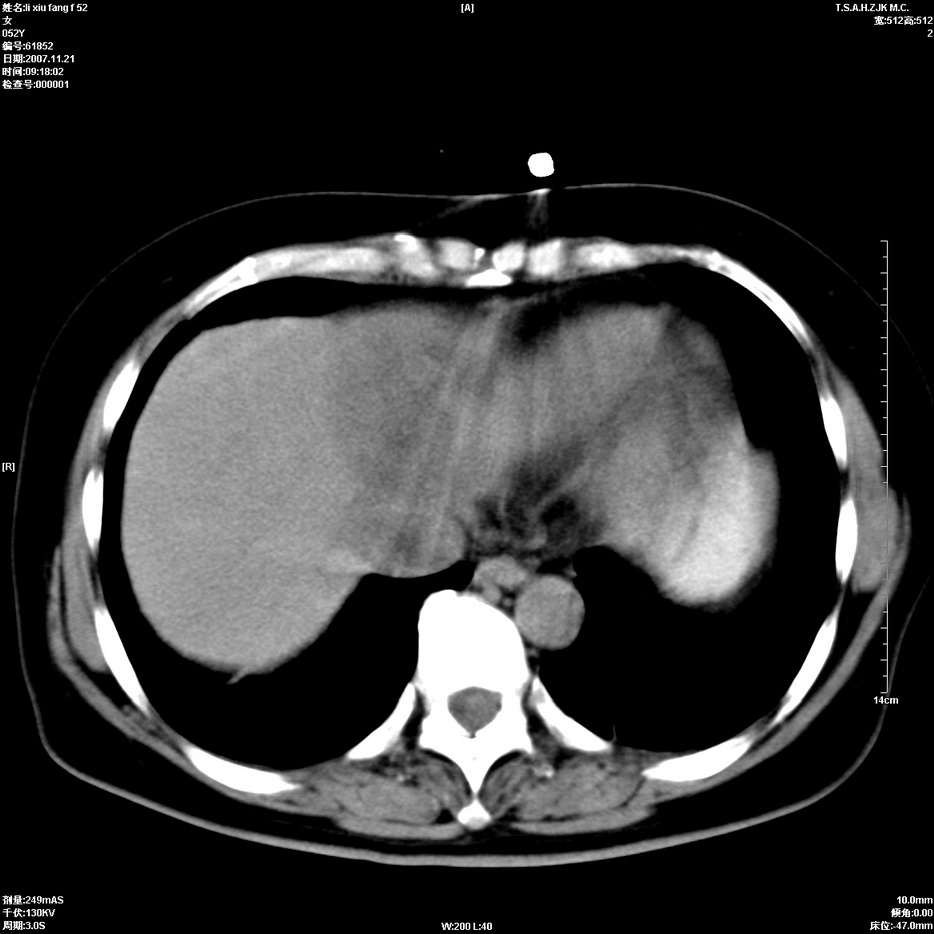

标题: CT12858:女,52岁,胎甲球蛋白861肝左叶占位,肝癌。下腔静 [打印本页]

标题: CT12858:女,52岁,胎甲球蛋白861肝左叶占位,肝癌。下腔静

肝左叶巨大低密度灶肿块,增强符合快进快出表现,有动静脉交通支;静脉期,下腔静脉内有充盈缺损,afp明显升高,支持肝癌并下腔静脉癌栓形成。

支持楼主   门静脉主干及左支癌栓形成

以下是引用拾荒者在2008-4-15 22:57:00的发言:[br]肝左叶巨大低密度灶肿块,增强符合快进快出表现,有动静脉交通支;静脉期,下腔静脉内有充盈缺损,afp明显升高,支持肝癌并下腔静脉癌栓形成。